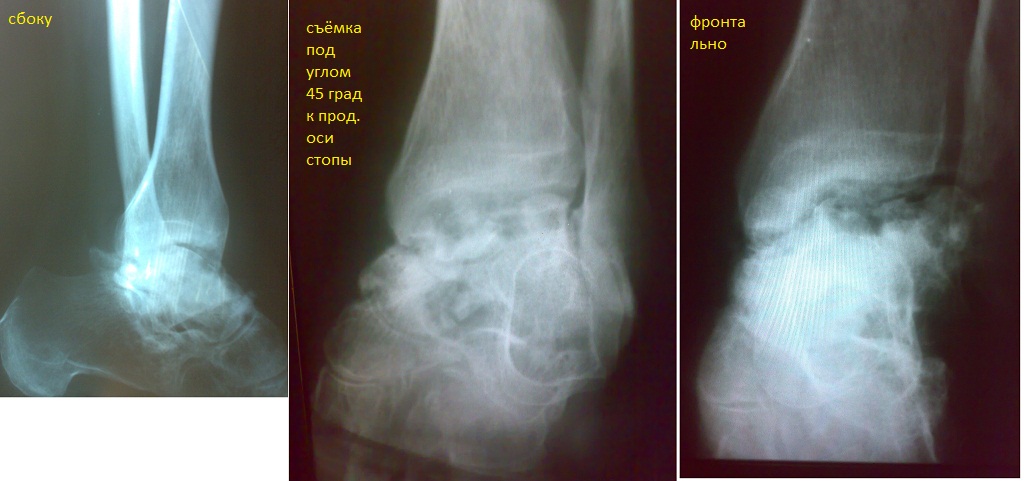

Доброго времени суток! 1.5 года назад получена травма (падение с высоты, МОС спицами,удалены через 1.5 месяца,всего в гипсе 3 мес),на ногу полностью долго не ставал-напугали артрозом, нагружал только физкультурой и массажами,постепенно начал приступать,после чего появлялись боли в суставе.Рекомендуют артродез,по сути ведь ампутацию сустава,неужели в 21 веке даже не сущесвует альтернативных идей?Сама по себе сейчас в состоянии покоя нога не болит,сгибается мышцами где-то на 5град.(при разработке-до 15-ти),разгибается в норме,но в последнее время увеличилась её кривизна, был установлен подвывих и нарушение оси нагрузки.Надеюсь,что если устранить это и выравнять сустав,он со временем вернётся к практически нормальной работе,учитывая высокую способность моего организма к восстановлению,относительно непожилой возраст-32 года,упорство в занятиях спортом,и желание выздороветь.Однако рекомендуют исключительно артродез(либо протез),по сути ведь ампутацию сустава,неужели в 21 веке даже не существует альтернативных идей? Уважаемые врачи, помогите, пожалуйста, разобраться,буду очень рад вашим ответам. Можно в почту-alxnd@i.ua

• Кликните для загрузки файла Л_готово_01-2011.jpg

136KB (140219 bytes)